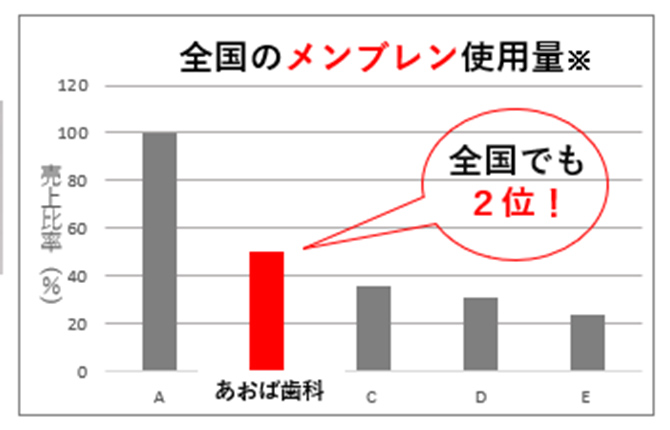

埼玉県内で

昨年も高い

再生医療実績(2025年)

| 前歯 | 小臼歯 | 大臼歯 | 合計 |

|---|---|---|---|

| 1,516本 | 683本 | 1,981本 | 4,180本 |

(歯科歴25年間に行った感染根管治療の本数は、約7,000本です)